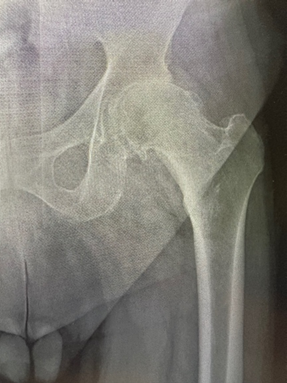

R: L'anca è l'articolazione formata da femore e osso iliaco. L’osso iliaco presenta una struttura concava, l'acetabolo, che rappresenta una sorta di tasca all'interno della quale si inserisce la testa del femore. Se l'anca è stata danneggiata da artrite, frattura, osteonecrosi, malattia dell'anca in età infantile o altre condizioni, le attività comuni come camminare o salire e scendere le scale, possono essere dolorose e difficili. L'anca potrebbe essere rigida con difficoltà nell’ indossare scarpe e calze. A volte si può avvertire disagio o dolore a riposo.

R: Si effettua una sostituzione totale dell'anca (chiamata anche artroplastica totale dell'anca), l'osso e la cartilagine danneggiati vengono rimossi e sostituiti con componenti protesici.

• La testa del femore danneggiata viene rimossa e sostituita con uno stelo di metallo che viene inserito nel centro cavo del femore. Lo stelo femorale può essere cementato o "inserito a pressione" nell'osso.

• Una sfera di metallo o ceramica è posta sulla parte superiore dello stelo. Questa sfera sostituisce la testa del femore danneggiata che è stata rimossa.

• La superficie cartilaginea danneggiata dell'alveolo (acetabolo) viene rimossa e sostituita con un alveolo metallico. A volte vengono utilizzate viti o cemento per tenere in posizione le varie componenti della protesi. Tra l’alveolo e la testa femorale in cromo o titanio, viene sempre utilizzato uno strato di polietilene preventivamente trattato con radiazioni per reticolare i radicali liberi nella plastica e così diminuire l'incidenza dell'usura dovuta a fenomeni di ossidazione. In altre parole, il trattamento con radiazioni, limita o rallenta il processo di usura e deterioramento del polietilene. In caso di deterioramento, grazie alla natura modulare di ogni componente, potrà essere necessario, col tempo, sostituire solo questa parte.